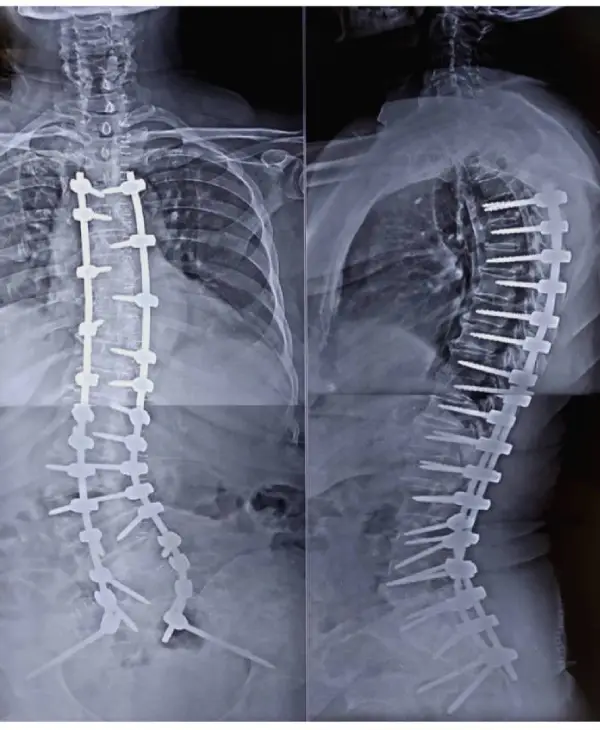

67 years old female presented with the complaints of low back ache radiating to posterior aspect of thigh for past 1 year. History of urinary incontinence (+) for the past 6 months & symptoms worsened for the past 2 months. She had difficulty in sitting, standing and walking on her own, and was totally dependent on care giver.

Diagnosis: Degenerative scoliosis

Treatment: D11 to L5 instrumented deformity correction, decompression and fusion.

Outcome: Patient was started on osteoporosis medications and has significant relief from leg symptoms. She is now an independent woman taking care of her activities of daily living.